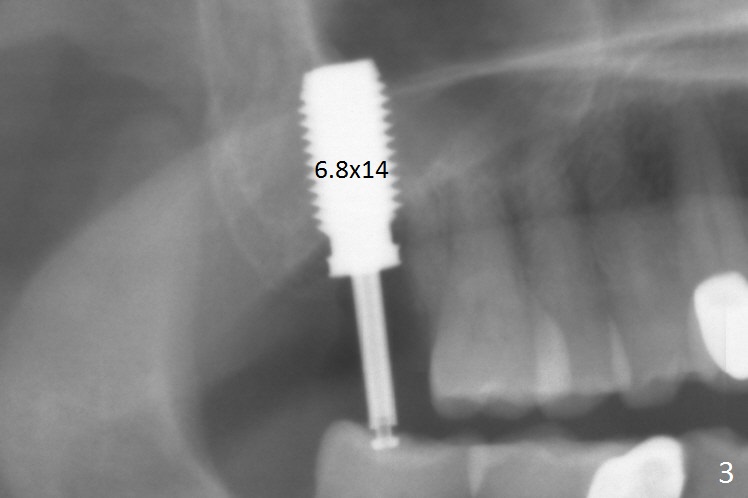

Preop exam shows that the tooth #2 has split into the buccal (Fig.1 B) and palatal (P) halves. When the tooth is extracted (Fig.2), there is a large piece of granulation tissue between these halves. The socket is large with sinus floor having pointed perforation. The latter is enlarged with rounded tapered Tatum osteotomy 2-4 mm, followed by tapered and then rounded taps. A 6.8x14 mm rounded tap has barely enough stability (Fig.3). Following placement of 2 PRF plug and 2 PRF membranes and allograft/Osteogen, a 8x17 mm cylindrical implant is placed with 60 Ncm (implant machine reading), however the implant is unstable (Fig.4). More graft is placed around the implant. With placement of 6x3 mm abutment, an immediate provisional is fabricated to close the socket. There is nasal discharge for a few days postop. PAs taken nearly 6 months postop show no bone loss (Fig.5,6). The definitive crown is cemented with access hole; there is no residual cement (Fig.7 (9 months postop)). The crown is loose 1 month post cementation (last March, Fig.8 with periimplant space (*)). The unipost was not cemented due to gag reflex. He refuses treatment immediately because of the allergy season. When he returns, spray a topical to his throat. Following crown removal, implant is found to have mobility. Panoramic X-ray (Fig.9) and CT (Fig.10,11) show fibrointegration (space) and implant intrusion into the sinus (S) without bone formation. After implant removal, the sinus floor and membrane are found to have been perforated. Osteogen plug is placed, followed by Vanilla/Osteogen (Fig.12 *) and Osteogen plug. It appears that an immediate implant is contraindicated when there is severe infection (Fig.2) with sinus floor perforation. In this case, the bone density at the upper 2nd molar is low (Fig.10 distopalatal view of 3-D image). Bone expansion and condensation is needed for implantation. Progressive loading is also necessity prior to impression.